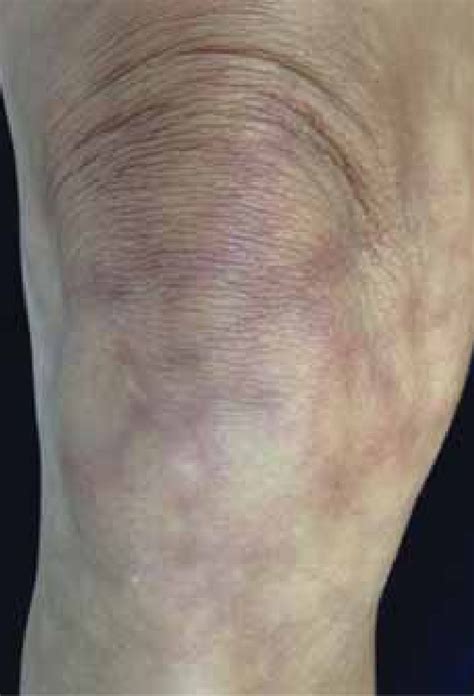

Livedo reticularis is a mottled, reticular discoloration of the skin, often appearing as a network of fine, bluish or purplish lines. This condition can be benign, but it can also be associated with various underlying medical conditions, making its identification and diagnosis crucial for proper management. In this article, we will delve into the world of livedo reticularis, exploring its causes, symptoms, diagnosis, and treatment options, along with providing a comprehensive overview of the condition through livedo reticularis photos.

Livedo reticularis is characterized by its unique appearance, which resembles a lace or fishnet pattern on the skin. It is caused by the slowing down or reduction of blood flow to the skin, which leads to the visibility of the blood vessels through the skin, creating the distinctive mottled appearance. This condition can affect various parts of the body, including the arms, legs, and torso. Livedo reticularis photos showcase the variability in presentation, from mild, barely noticeable changes to more pronounced, widespread discoloration.

The causes of livedo reticularis can be broadly categorized into primary and secondary. Primary livedo reticularis is often benign and idiopathic, meaning its cause is unknown, and it may be influenced by cold temperatures or other environmental factors. Secondary livedo reticularis, however, is associated with underlying medical conditions, such as autoimmune diseases (e.g., lupus, rheumatoid arthritis), vasculitis, and neurological disorders. Certain medications and infections can also lead to livedo reticularis. A thorough examination of livedo reticularis photos can help differentiate between the primary and secondary forms, guiding further diagnostic investigations.

Diagnosing livedo reticularis involves a combination of clinical examination, medical history, and sometimes, additional diagnostic tests to rule out underlying conditions. Livedo reticularis photos can aid in the initial assessment, helping to identify the characteristic pattern and distribution of the discoloration. Management strategies depend on the underlying cause; for primary livedo reticularis, measures to improve circulation and protect the skin from cold may be sufficient. For secondary livedo reticularis, treatment focuses on addressing the associated medical condition, which may involve medication, lifestyle changes, or other interventions.